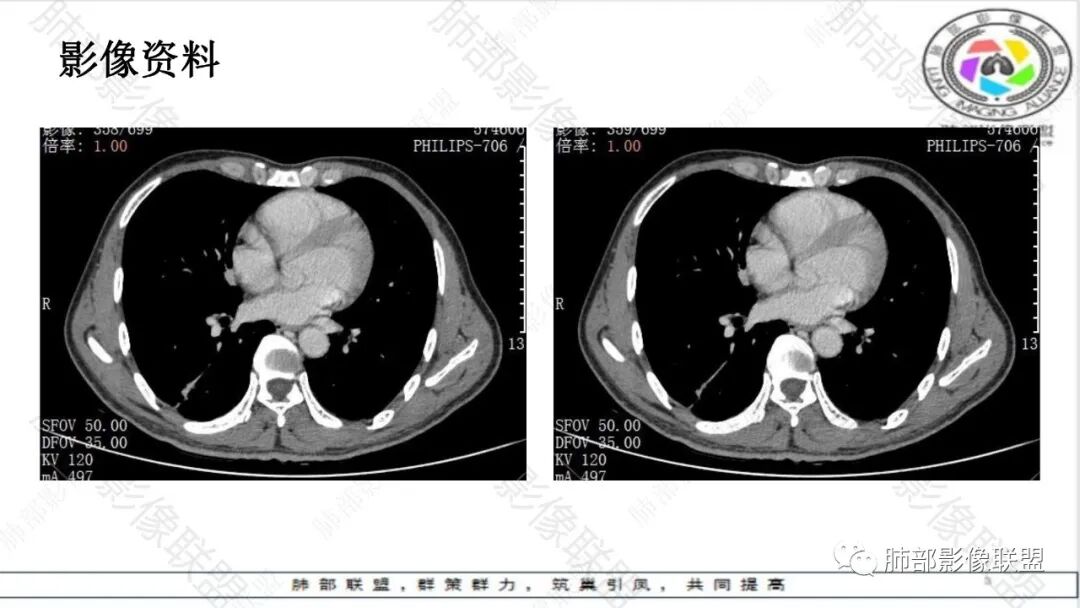

1.病例特点:中老年男性,长期睡眠异常(嗜睡),焦虑状态。病例右肺下叶长条片状病灶,实性密度为主,轻度强化,边缘多平直(可见尖角征),未见明显膨隆分叶及毛刺,边缘见模糊磨玻璃影,未见钙化、液化或空洞。病灶长轴顺延下叶支气管方向,长索条状牵张于胸壁肺门间,轻度胸膜凹陷。病灶内见支气管、血管通行,气管略壁厚。

未见卫星病灶,未见“树芽征”或拐枣样改变“拐枣征”。未显示新旧不等改变。

右肺门及纵膈未见肿大淋巴结。

2.综合分析:条片状病灶,边缘平直,尖角,未见典型的分叶毛刺,少张力,也未见边界清楚的磨玻璃晕,同侧肺门及纵隔未见增大淋巴结等等,总之,如多数老师分析,缺乏典型恶性肿瘤影像学特征。

病灶相对孤立,未见钙化或新旧不等,未见“树芽征”或“拐枣征”,亦未见典型继发性肺结核影像学特点。